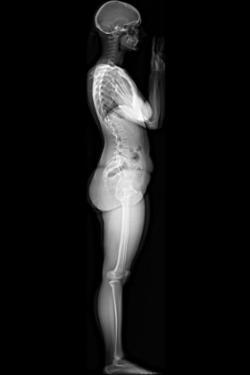

The EOS system provides full-body stereo-radiographic images of patients in functional positions, in both 2-D and 3-D, as well as related software solutions. EOS exams require a radiation dose 50-85 percent less than digital radiology and 95 percent less than basic computed tomography (CT) scans. The new EOS Micro Dose option, recently cleared by the U.S. Food and Drug Administration, allows a further drastic step towards the ALARA (As Low As Reasonably Achievable) principle by bringing pediatric spine follow-up exams at a dose level equivalent to a week of natural background radiation on Earth.